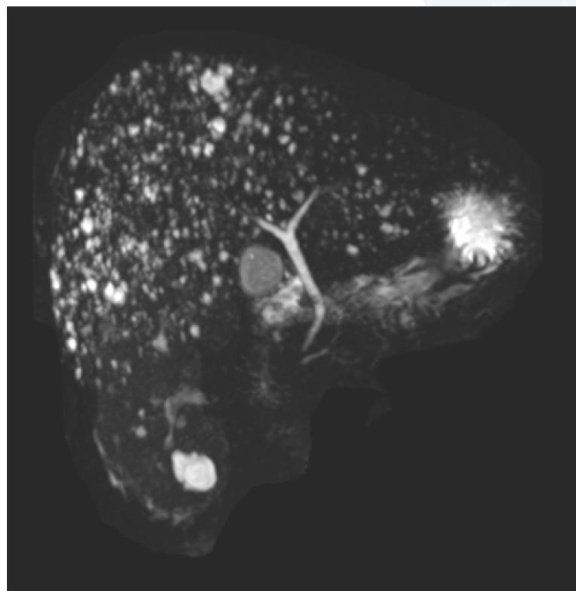

图1肝脏核磁共振见弥漫分布小圆形信号,呈“满天星征”

肝脏内发现数百个结节,核磁共振成像中宛如满天繁星,这究竟是什么疾病?是否可治?这一疾病医学上称为“胆管错构瘤”,是一种较为罕见的肝脏良性病变。该病变主要发生在胆管系统,因正常组织发生异常组合形成,本质并非真性肿瘤,不具备侵袭转移能力。胆管错构瘤多通过影像学检查偶然发现(图1),因缺乏典型临床症状,其诊断与临床管理具有一定挑战性。(剩余1600字)